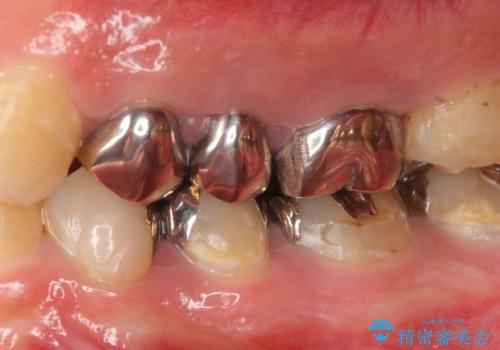

- 左上奥歯の銀歯をセラミックにしたいといらっしゃった方の症例です。

銀歯を除去したところ歯茎よりも深い位置まで虫歯があったため、歯冠長延長術(歯周外科)を行いました。

その後歯茎の回復を待つ間に再根管治療を行い、歯茎の回復後オールセラミッククラウンにて補綴を行いました。